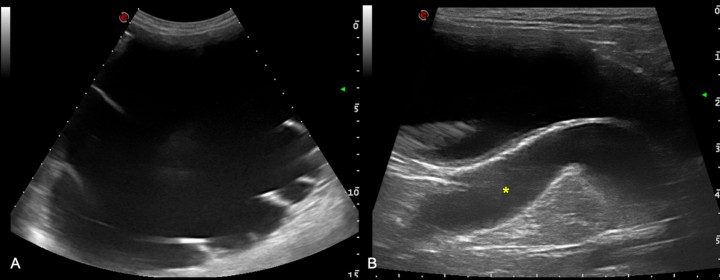

Se realiza una ecografía abdominal mediante sonda microcónvex que evidencia una severa dilatación de la pelvis renal derecha, con contenido anecoico, que provoca una reducción grave de la capa cortical (atrofia cortical) (Fig. 3A), asociada con un hidrouréter derecho (dilatación de hasta 15 mm) y con su inserción anómala en la uretra prostática (Fig. 3B). El riñón izquierdo presenta una arquitectura ecográfica normal, con buena definición corticomedular, sin alteraciones en el sistema colector y sin alteraciones asociadas con el uréter izquierdo.

<p>Imágenes ecográficas. (<strong>A</strong>) Hidronefrosis en riñón derecho con resto de cortical. (<strong>B</strong>) Dilatación grave del uréter derecho hacia su desembocadura en la uretra prostática (asterisco amarillo).</p>

Imágenes ecográficas. (A) Hidronefrosis en riñón derecho con resto de cortical. (B) Dilatación grave del uréter derecho hacia su desembocadura en la uretra prostática (asterisco amarillo).

Por lo tanto, el estudio ecográfico es compatible con hidronefrosis con hidrouréter y ectopia ureteral derecha.